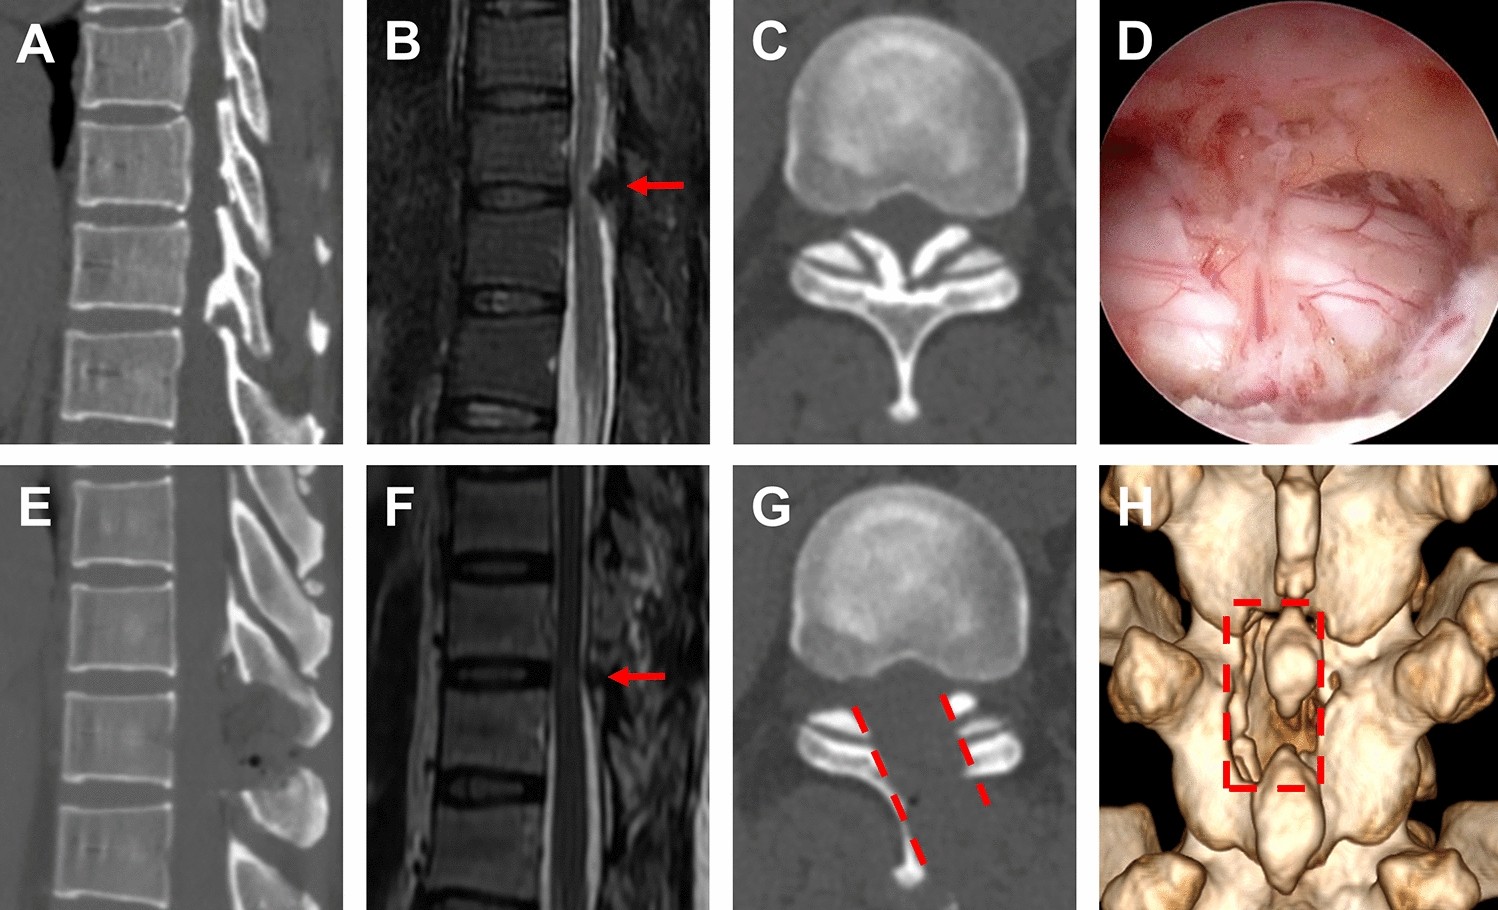

Figure 2

Single segment TOLF treated with OSE procedure. (A–C) Preoperative sagittal, axial CT and MRI images of TOLF, and the ossification lesion compressed the spinal cord at T10/11 (As shown by the red arrow). (D) The view of decompression of spinal cord during operation on endoscope. (E–G) Postoperative sagittal, axial CT and MRI images, demonstrated a complete remove of ossification lesion (As shown by the red arrow and dashed). (H) Postoperative 3D-CT image showed the range of unilateral laminectomy at T10 and T11 (As shown in the red dashed region), bilateral decompression of spinal cord through unilateral approach.